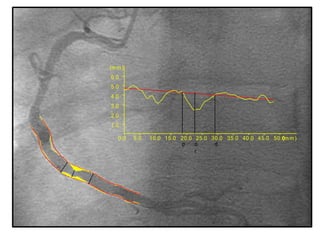

Quantitative Coronary Angiogram

• 2 Dimensional & 3 Dimensional.

• Earlier manually done by calipers later done through

computers.

• Invented by Greg Brown in University of Washington

30 yrs back

• Good quality angiograms at least two orthogonal views

required to avoid

foreshortening, vessel overlapping, irregular margins.

3 D imaging utilizes standard 2 D images 30` apart and

reconstructs

0.0 5.0 10.0 15.0 20.0 25.0 30.0 35.0 40.0 45.0 50.0(m m )

1.0

2.0

3.0

4.0

5.0

6.0

(m m )

op d

r

QCA

Quantitative Coronary Angiogram •2 Dimensional & 3 Dimensional. • Earlier manually done by calipers later done through computers. • Invented by Greg Brown in University of Washington 30 yrs back • Good quality angiograms at least two orthogonal views required to avoid foreshortening, vessel overlapping, irregular margins. 3 D imaging utilizes standard 2 D images 30` apart and reconstructs

0.0 5.0 10.015.0 20.0 25.0 30.0 35.0 40.0 45.0 50.0(m m ) 1.0 2.0 3.0 4.0 5.0 6.0 (m m ) op d r